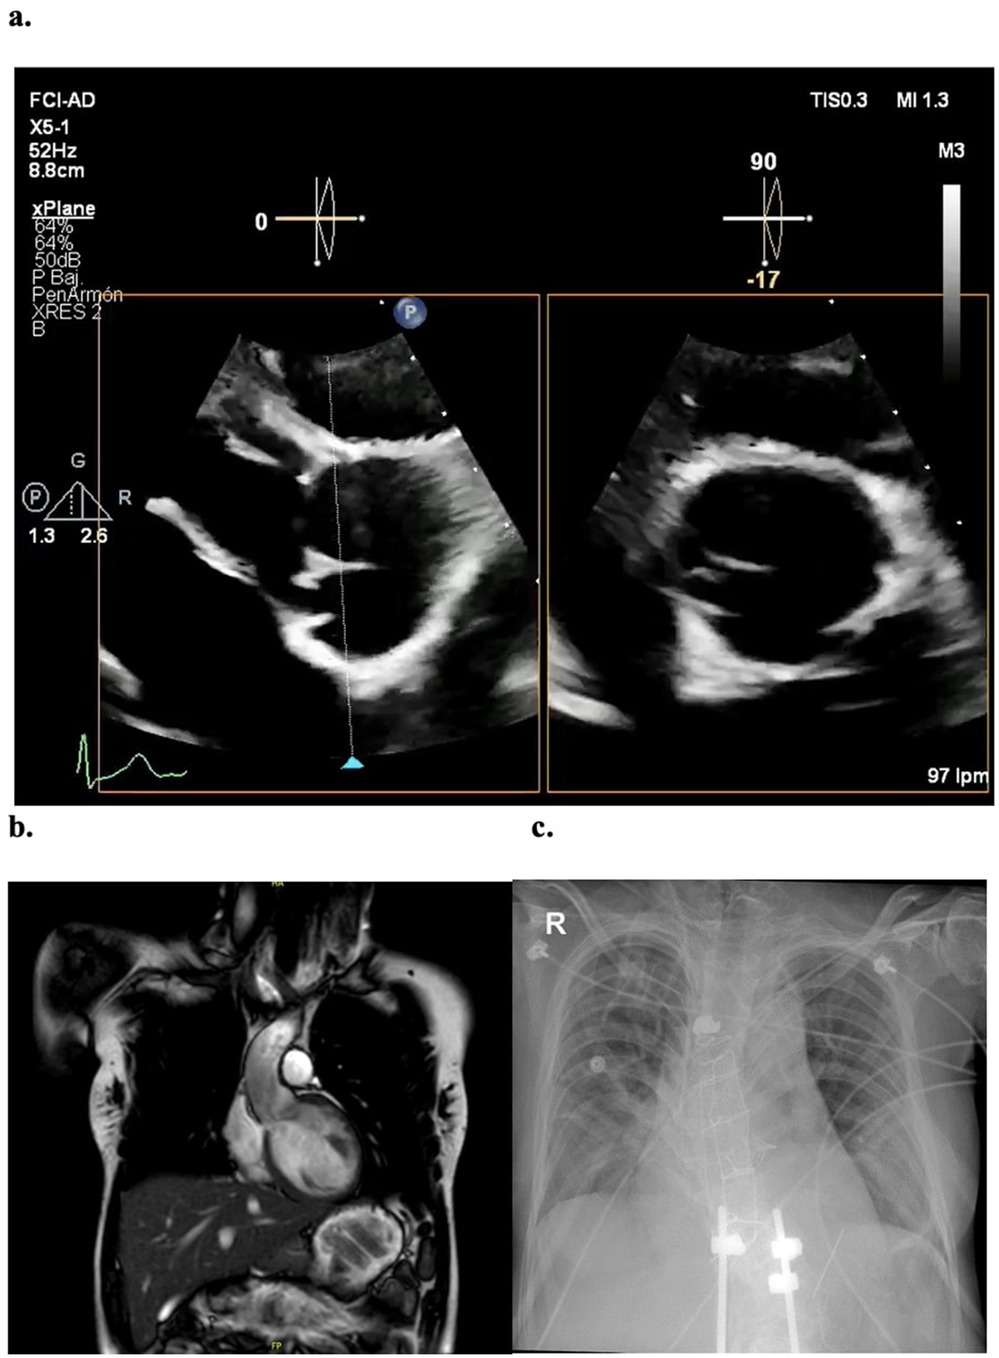

Preoperative echocardiogram (Figure 1a) showed a severely dilated left ventricle with eccentric hypertrophy, LVEF 60%, and severe aortic regurgitation. The aortic root measured 36 mm. Cardiac MRI confirmed the findings with a regurgitant fraction of 59%. The ascending aorta was measured at 30 × 30 × 30 at the highest diameter (commissural level) (Figure 1b). Ergospirometry revealed no limitations in cardiovascular or pulmonary function.

Figure 1

Imaging studies (a) preoperative transthoracic echocardiogram, with severe aortic regurgitation associated to a non-coronary cusp retraction. (b) Coronal view of Cardiac MRI, showing a non-dilated ascending aorta with maximum commissural diameter of 30 mm (c) postoperative x-ray evidencing 6 surgical steel wire sutures and sternal hemi cerclage.